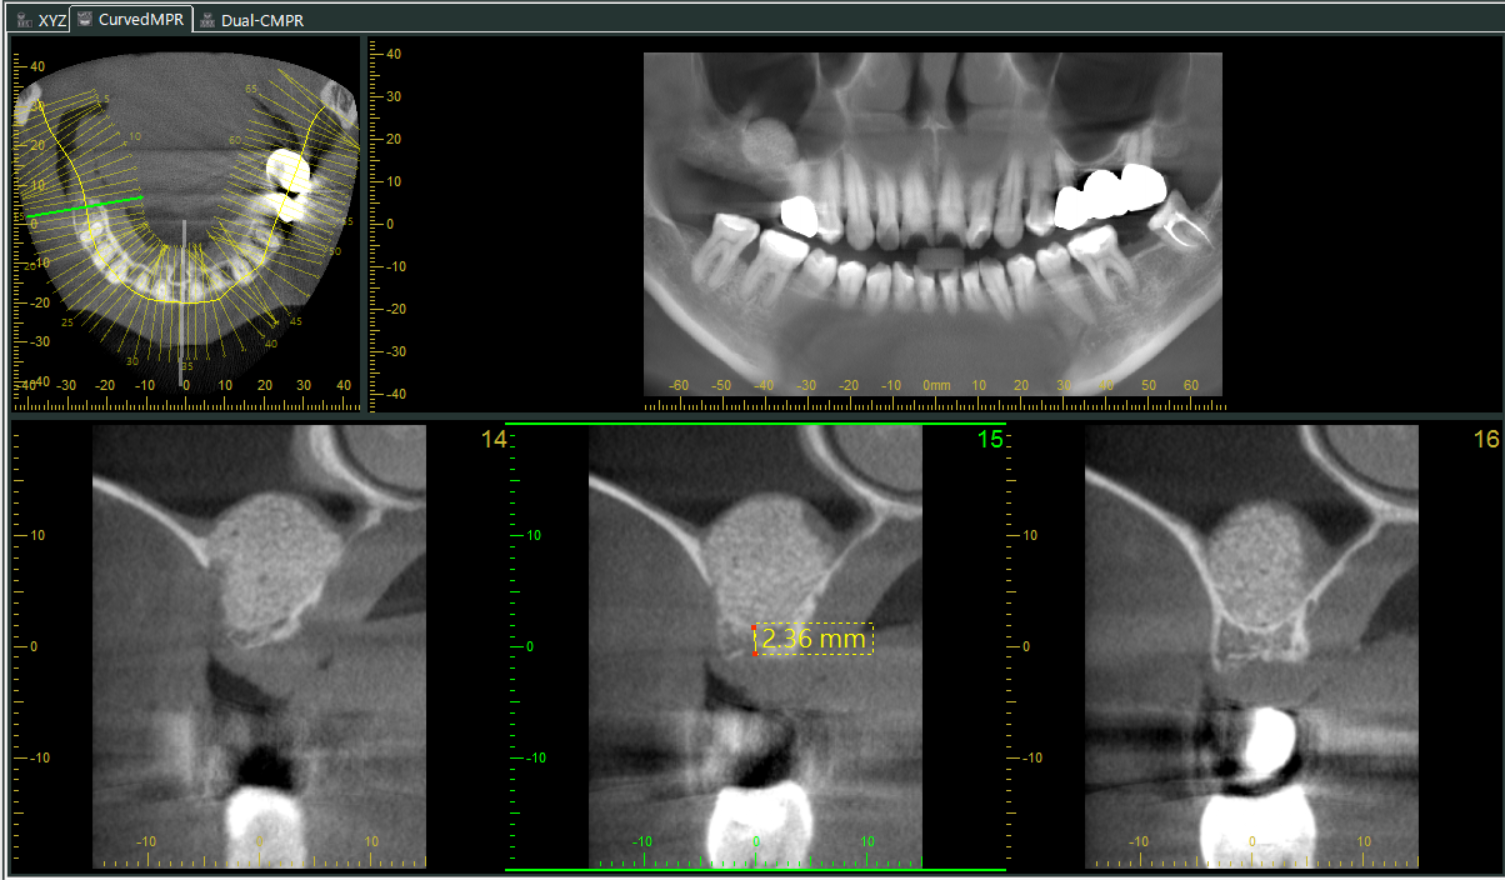

導航植牙,也叫做「4D動態導航植牙」,其實就是利用高科技來幫助我們更精準地完成植牙手術,簡單來說,就是在手術前會先幫你做電腦斷層(CT)、數位口腔印模,把你的骨頭、神經、血管、口腔等重要結構都看得很清楚,然後用電腦軟體中預先規劃未來假牙位置、植體植入的深度及角度,模擬出植牙的最佳路徑做定位,降低植牙療程中的誤差,有效提高治療的成功率並減少植牙後遺症,達到真正的數位植牙。

日本Morita3D電腦斷層 提供3D立體影像,可從多角度觀察齒槽骨、鼻竇、神經位置。 |

將數位資料匯入專業植牙規劃軟體,在電腦上進行精密的「虛擬手術」,預先設定好植體的最佳位置、角度、深度。

使用植牙導航,手術資訊與數位檔案同步顯示在電腦畫面上,使醫生能更快速、精準、安全的將植體放到目標位置。

▲使用導航技術,可以手術當下即時反映出植牙鑽針的角度、深度、位置等資訊,精準定位植體位置。